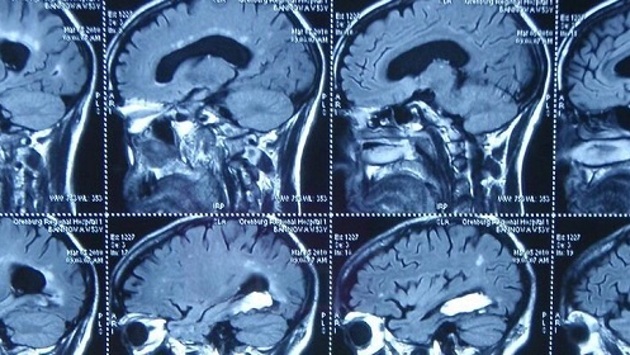

По данным ТАСС, программа анализирует 2- или 3-мерные модели на основе предварительной обработки данных нескольких снимков МРТ мозга. Цифровые модели эффективно и точно определяют четыре вида опухолей: менингиому, невриному, глиобластому и астроцитому, их строение, содержание и габариты.

Программа находится в свободном пользовании. Известно, что точность обработки данных составляет 92% (по метрике Дайса). После тестирования программный модуль будет внедрен в работу лечебных учреждений.